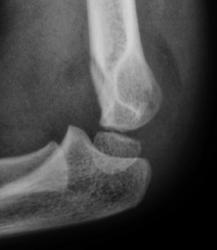

Пол пациента: Мужской пол Тип патологии: Травма Область исследования: Скелетно-мышечная система Методы исследования: Rg Рентгенограммы произведены в "ургентном" порядке ургентным лаборантом. Пациент направлен на исследование дежулным хирургом. ВАШЕ МНЕНИЕ КОЛЛЕГИ? TRAVMA.1..JPG TRAVMA_2..jpg TRAVMA.3..jpg TRAVMA.4..JPG TRAVMA.5..JPG AttachmentSize TRAVMA.1..JPG45.46 KB TRAVMA_2..jpg78.72 KB TRAVMA.3..jpg82 KB TRAVMA.4..JPG57.79 KB TRAVMA.5..JPG76.83 KB Mon, 16/11/2009 - 18:06 #1 v1tal Offline Last seen: 4 years 10 months ago Joined: 07.06.2008 - 19:41 Posts: 1779 Супракондилярный перелом дистального эпифиза плечевой кости, с незначительным угловым смещением открытым кзади. "Знаешь, у некоторых врачей есть комплекс мессии — им необходимо спасать мир. А у тебя комплекс Рубика — тебе необходимо решать головоломки." Mon, 16/11/2009 - 22:39 #2 В.Б. Серов Offline Last seen: 3 weeks 6 days ago Joined: 16.07.2008 - 10:15 Posts: 1361 Перелом вижу, смещения - нет Зри в корень! Mon, 16/11/2009 - 23:06 #3 Анатолий Владим... Offline Last seen: 7 years 10 months ago Joined: 16.10.2009 - 21:16 Posts: 1941 А смещение действительно минимальное.

Супракондилярный перелом дистального эпифиза плечевой кости, с незначительным угловым смещением открытым кзади.

Перелом вижу, смещения - нет

А смещение действительно минимальное.